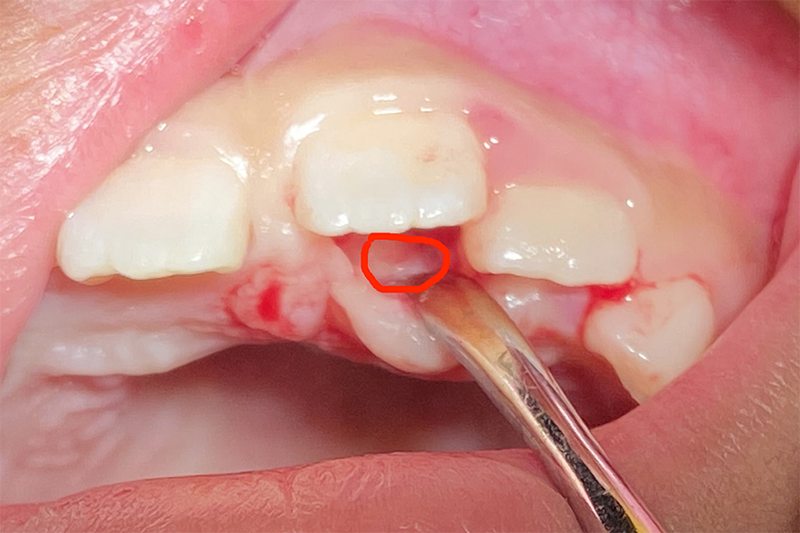

【被拔除的多生牙】

在门诊手术室,术中局麻后,陈琦顺利为文文拔除了多生牙。因为是微创小手术,切口小无须缝合,也保住了未来恒牙的正常发育。